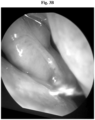

FIG. 3A represents an endoscopic photograph of the sinus of Patient 11 of Example 2 prior to treatment with the cream composition as described in Example 1.

• FIG. 3 A shows the left nasal cavity with the middle turbinate noted in the circle. The middle turbinate shows significant hyperemia, edema, granulation changes with minor bleeding.

• FIG. 3 B shows a reduction in all of the diseased changes noted prior to treatment most notably reduction in general inflammatory response highlighted by reduction in hyperemia, edema and granulation changes.